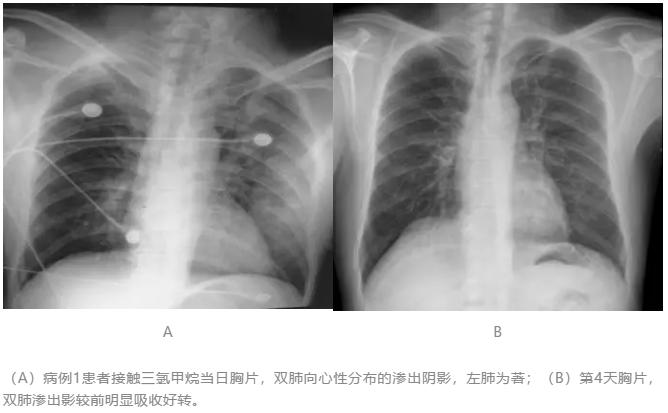

【图1】后前位X线胸片

(A)病例1患者接触三氯甲烷当日胸片,双肺向心性分布的渗出阴影,左肺为著;(B)第4天胸片,双肺渗出影较前明显吸收好转。